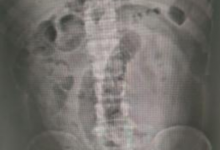

男子连吃3根生香蕉致肠梗阻 网友:还是火龙果好使-融党建互动平台

男子连吃3根生香蕉致肠梗阻 网友:还是火龙果好使

admin阅读(249)赞(0)

近日,广东东莞,张先生下班后实在太饿,连吃3根没有完全成熟的香蕉,又喝了牛奶。2个小时后张先生腹痛难忍,被诊断为肠梗阻。   医生介绍,香蕉中膳食纤维含量其实并不高,不能缓解便秘,如果吃了没熟透的青香蕉,其中含大量鞣酸,与蛋白质等聚合在...